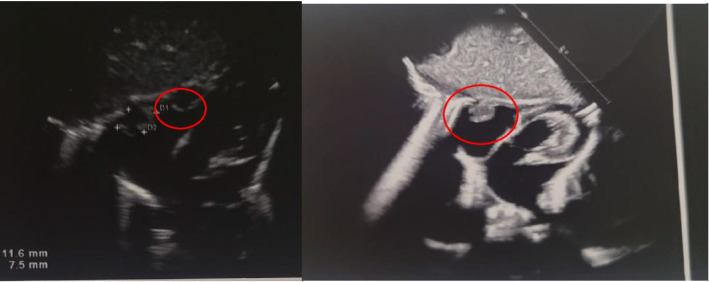

Background: Infantile myofibromatosis, a rare soft tissue neoplasm that may present at birth or in early infancy, is the most common fibrous tumor of infancy and early childhood. Diagnosis could be challenging due to different clinical presentation. Very few cases are detected prenatally and visceral involvement is extremely rare.

Case presentation: We present a case of Disseminated Infantile Myofibromatosis with challenging prenatal ultrasound and misleading clinical presentation. Diagnosis was very difficult and confirmed by pathology results obtained after birth.